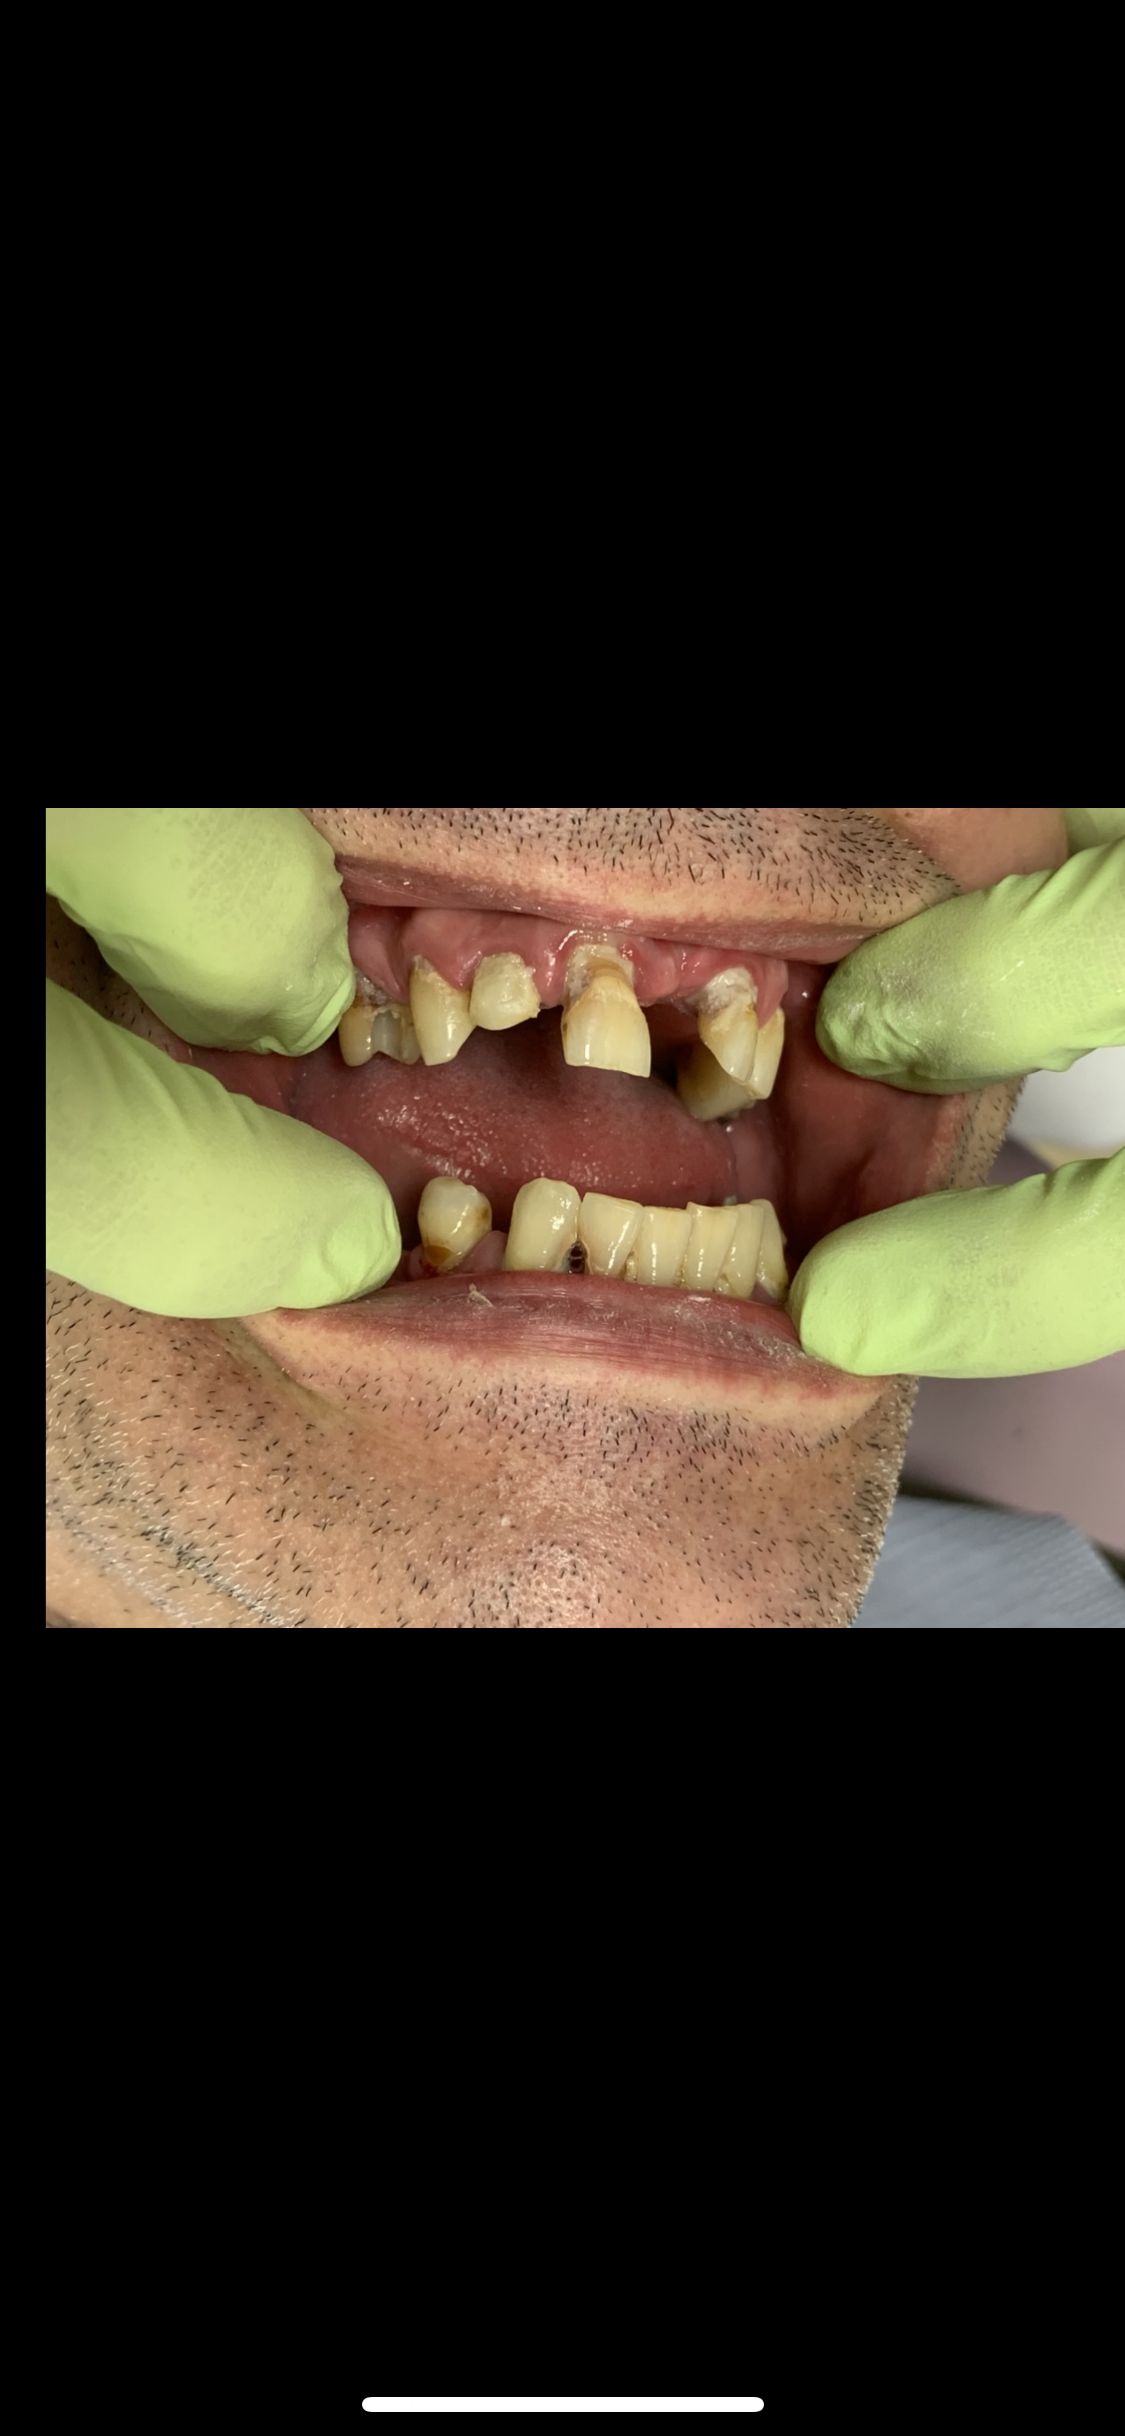

Ukończyłem Łódzką Akademie Medyczna, na wydziale stomatologicznym . W 2007 roku uzyskałem tytuł specjalisty w dziedzinie protetyki stomatologicznej. Regularnie pogłębiam wiedze z zakresu stomatologii o czym świadczą zdobyte przeze mnie certyfikaty . W chwili obecnej prowadzę NZOZ Duodent , specjalistyczny gabinet protetyczny na Widzewie - wschodzie , przy ul. Gogola 12 . Znajdują sie tu trzy nowocześnie urządzone i wyposażone gabinety stomatologiczne. Pracujemy na sprzęcie Sterna Webera, prestiżowej szwajcarskiej firmy produkującej unity stomatologiczne...W gabinecie znajduje sie skaner wewnątrzustny MEDIR i 500 R , gdyz obecnie gabinet nasz wyspecjalizował sie w PROTETYCE CYFROWEJ

Pan dok.Polakowski to profesjonalista, tam gdzie nikt nie chciał zająć się moimi zębami

P.dok wyczarowal piękny uśmiech.

Dziękuję, i z czystym sumieniem mogę polecić każdemu kto ma problemy z zębami.

• Duo-Dent odbudowa zębów  •